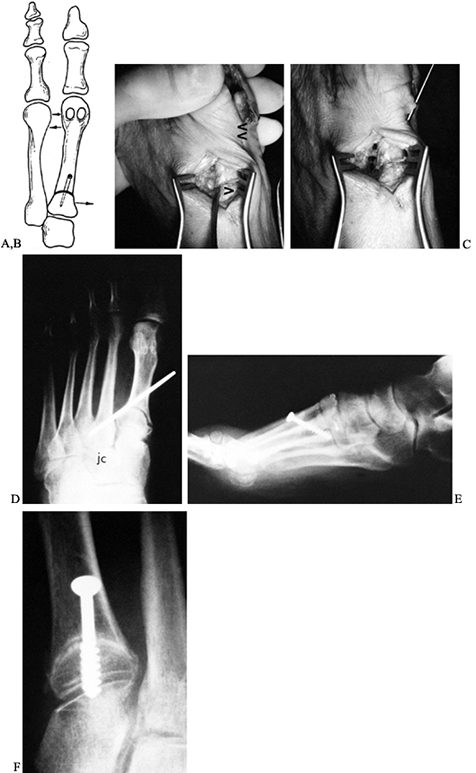

metatarsus primus varus (Fig. 112.11). We prefer to stabilize the osteotomy site with a 4.0 mm, cannulated AO screw, although an oblique 5/564-inch Steinmann pin or multiple smaller K-wires may be used.

Figure 112.11.

The osteotomy site is reduced by completely freeing the soft tissue

about the osteotomy, then pushing the proximal fragment medially with a

small Freer elevator while pushing the metatarsal head laterally. This

locks the lateral aspect of the osteotomy site, and the internal

fixation is inserted. A: Drawing shows the bones involved. B,C,D: Fixation of the osteotomy site using an oblique 5/64-inch Steinmann pin. E,F: Fixation of the osteotomy site using a 4.0 mm screw. -